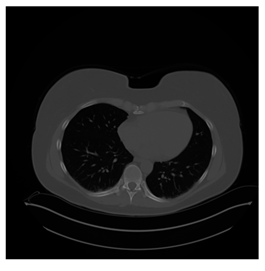

Figure 12.

Sampled images in the tested benchmark databases: (a) Breast-MRI-NACT-Pilot (breast), (b) ACRIN-DSC-MR-Brain (brain), (c) NIH (chest), (d) Lung-PET-CT-Dx (lung), (e) Prostate-MRI (prostate), and (f) Other grayscale standard images.

- Lung-PET-CT-Dx Database (available at: https://wiki.cancerimagingarchive.net/pages/viewpage.action?pageId=70224216 (accessed on 4 November 2021))

Lung-PET-CT-Dx is a CT-type image database collecting lung medical images. Some samples are shown in Figure 12d.